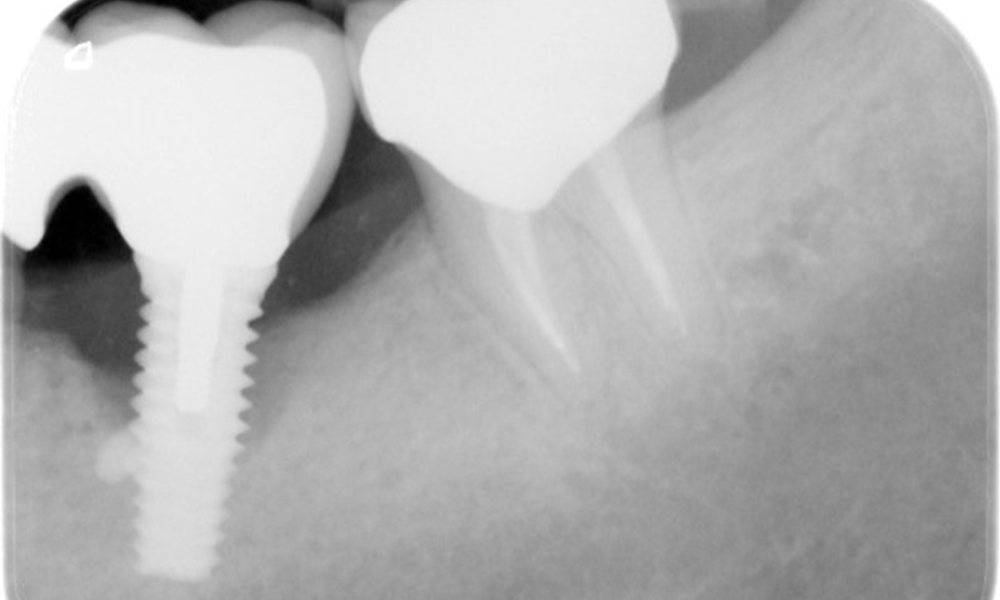

Ein 52-jähriger Patient stellt sich zur Präventionssitzung vor. Der Patient hat keine Allgemeinerkrankungen und nimmt keine Medikamente ein. Er hat verschiedene zahnärztliche Versorgungen und zudem zwei aktive kariöse Läsionen. Außerdem verfügt der Patient über vier Implantate (2., 3. und 4. Quadrant). Es zeigt sich eine parodontale Vorerkrankung (Stadium IV, Grad B). Derzeit herrschen stabile parodontale Verhältnisse, lediglich am Implantat regio 36 zeigen sich Sondierungstiefen (ST) von 5 mm. Zudem lässt sich eine Gingivitis feststellen.

Der Patient zeigt keine besonderen anamnestischen Risikofaktoren mit spezifischen zahnmedizinischen Auswirkungen. Daher ist der aus der Mundgesundheit ermittelte Bedarf maßgebend. Hierbei zeigt sich am Implantat im 3. Quadranten ST von 5 mm und im Röntgenbild eine Zunahme des Knochenverlustes. Der Patient hat zudem eine aktuell stabile parodontale Vorerkrankung und zwei aktive initialkariöse Läsionen.